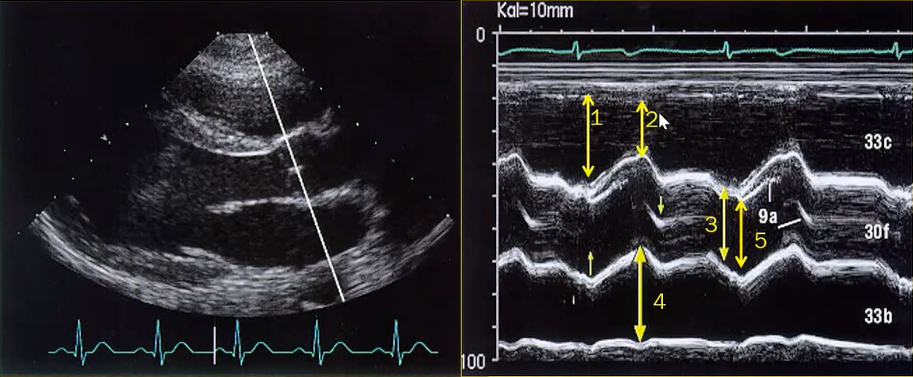

| 2.1. Mặt cắt trục dài cạnh ức với depth sâu

Cửa sổ siêu âm cạnh ức

Mặt cắt trục dài cạnh ức Đầu dò đặt tại bờ trái xương ức với marker hướng lên vai phải của bệnh nhân. |

| 2.2. Mặt cắt trục dài cạnh ức khu trú vào thất trái

Cửa sổ siêu âm cạnh ức

Mặt cắt trục dài cạnh ức Đầu dò đặt tại bờ trái xương ức với marker hướng lên vai phải của bệnh nhân. Chùm siêu âm đặt vuông góc với thất trái. |

Nhĩ trái (LA)

Van hai lá (MV) Thất trái (LV) Đường ra thất trái (LVOT) Van động mạch chủ (AV) Vách liên thất (IVS) Thất phải (RV) |